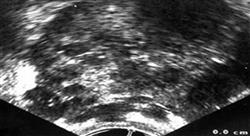

L’objectif de ce Certificat en Tumeurs Génito-Urinaires est d’actualiser les connaissances des étudiants sur les concepts et les critères de diagnostiques internationaux, afin de réaliser un diagnostic correct des tumeurs malignes ovariennes, et en suivant le classement de la World Health Organization (WHO/IARC 4e édition, 2014) et de l’International Federation of Gynecology and Obstetrics (FIGO).

Le Certificat en Tumeurs Génito-Urinaires est une formation spécialisée pour les professionnels médicaux impliqués dans le traitement des patients atteints de cancer de l'appareil génito-urinaire. Les patients atteints de cancer sont des patients présentant une complexité médicale importante, c'est pourquoi ils nécessitent une prise en charge multidisciplinaire par différents professionnels de santé. La mise à jour constante des avancées scientifiques est essentielle pour offrir des diagnostics et des traitements plus efficaces et pour améliorer la qualité de vie des patients. Ce Certificat en Tumeurs Génito-Urinaires, une pathologie qui affecte une partie importante de la population et dont le diagnostic et le traitement requièrent un haut degré de Spécialisez-vous. Au cours du programme, les étudiants apprendront les dernières avancées en matière de techniques de diagnostic et de traitement des tumeurs génito-urinaires, telles que le cancer de la prostate, de la vessie ou du rein.

Améliorez le traitement de vos patients en oncologie